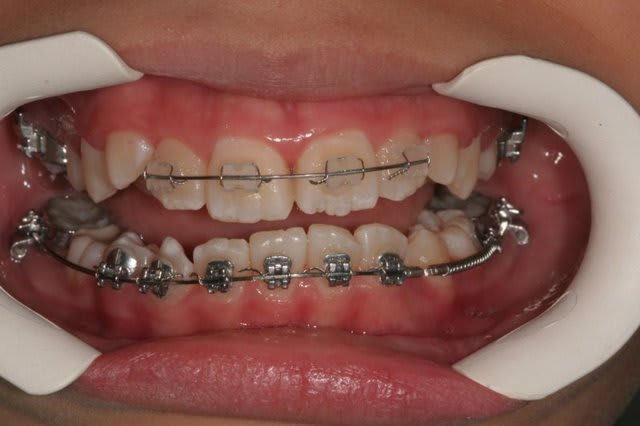

j'ai revu le jeune patient(7,5 ans) aujourd'hui.

En fait, il porte un multi bagues sur les 4inc associé à un quadhélix.

C’est la technique segmentée de Ricketts.

Technique utilisée en interception, elle a pour but de corriger très tôt les axes des incisives.

Et par le Q.H. de déroter les 6 (canines postérieures) pour déverrouiller la croissance, ainsi que de verser les dents lactéales qui vont entraîner les germes des dents permanentes et ainsi faire une expansion avec de l’os.

C’est une excellente technique d’interception, bien que pas toute jeune. C’est dommage que tu n’en ais pas vu plus souvent.

Les douleurs viennent souvent du Q.H. qui en travaillant peut appuyer sur le palais, ou des crochets extérieurs sur les bagues.